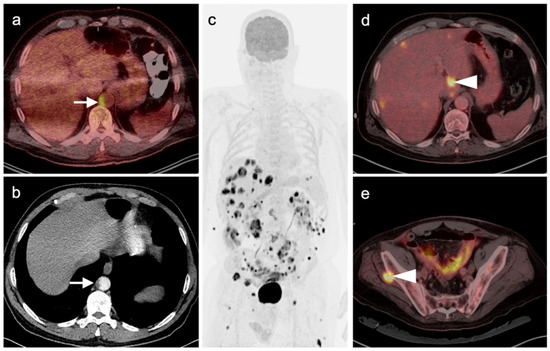

4.3. Gastroenteropancreatic (GEP) Neuroendocrine Tumors

4.4. Bronchial Carcinoid

4.5. Pheochromocytoma and Paraganglioma